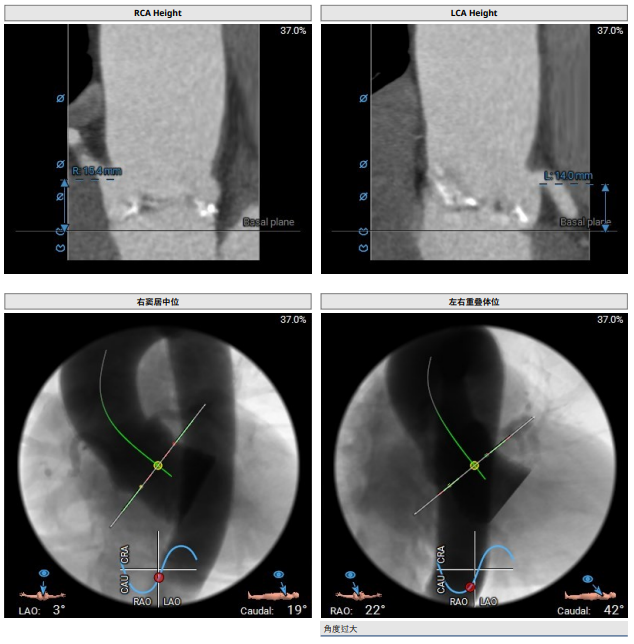

主动脉根部:功能型二叶瓣,瓣叶增厚,重度钙化,左右可见钙化融合。左冠开口高度约14mm,右冠开口高度约15.4mm。法式窦结构大,STJ高度约20.2mm、直径约30.6mm。升主动脉未见明显扩张,心脏角度约54°。左室大小尚可,心肌增厚。CT显示患者结构偏大,瓣环及流出道成敞口状。瓣上各辅助锚定区域处于临界值,给手术操作带来挑战。 请注意,我没有改变原文的意思。

功能型二叶瓣,瓣叶增厚,重度钙化,左右可见钙化融合,左冠开口高度约1 4mm,右冠开口高度约1 5.4mm,法式窦结构大,STJ高度约20.2mm、直径约30.6mm,升主动脉未见明显扩张,心脏角度约54°,左室大小尚可,心肌增厚。CT显示患者结构偏大,瓣环及流出道成敞口状,瓣上各辅助锚定区域处于临界值,给手术操作带来挑战

1患者患有功能型二叶瓣,瓣叶增厚,左右瓣叶间有钙化融合。左冠开口高度为14mm,右冠开口高度为15.4mm。法式窦结构较大,平均径为35.1mm。STJ高度为20.2m,直径为30.6mm。经过综合评估,在瓣膜释放过程中,位置难以控制,存在下滑移位甚至瓣中瓣的风险。

2心脏角度为54度,偏向横位,心脏输送器增加了瓣膜释放的难度。在瓣膜释放时,瓣膜与瓣环的同轴性较差。因此,我们选择使用VenusA-Pro第三代输送系统。